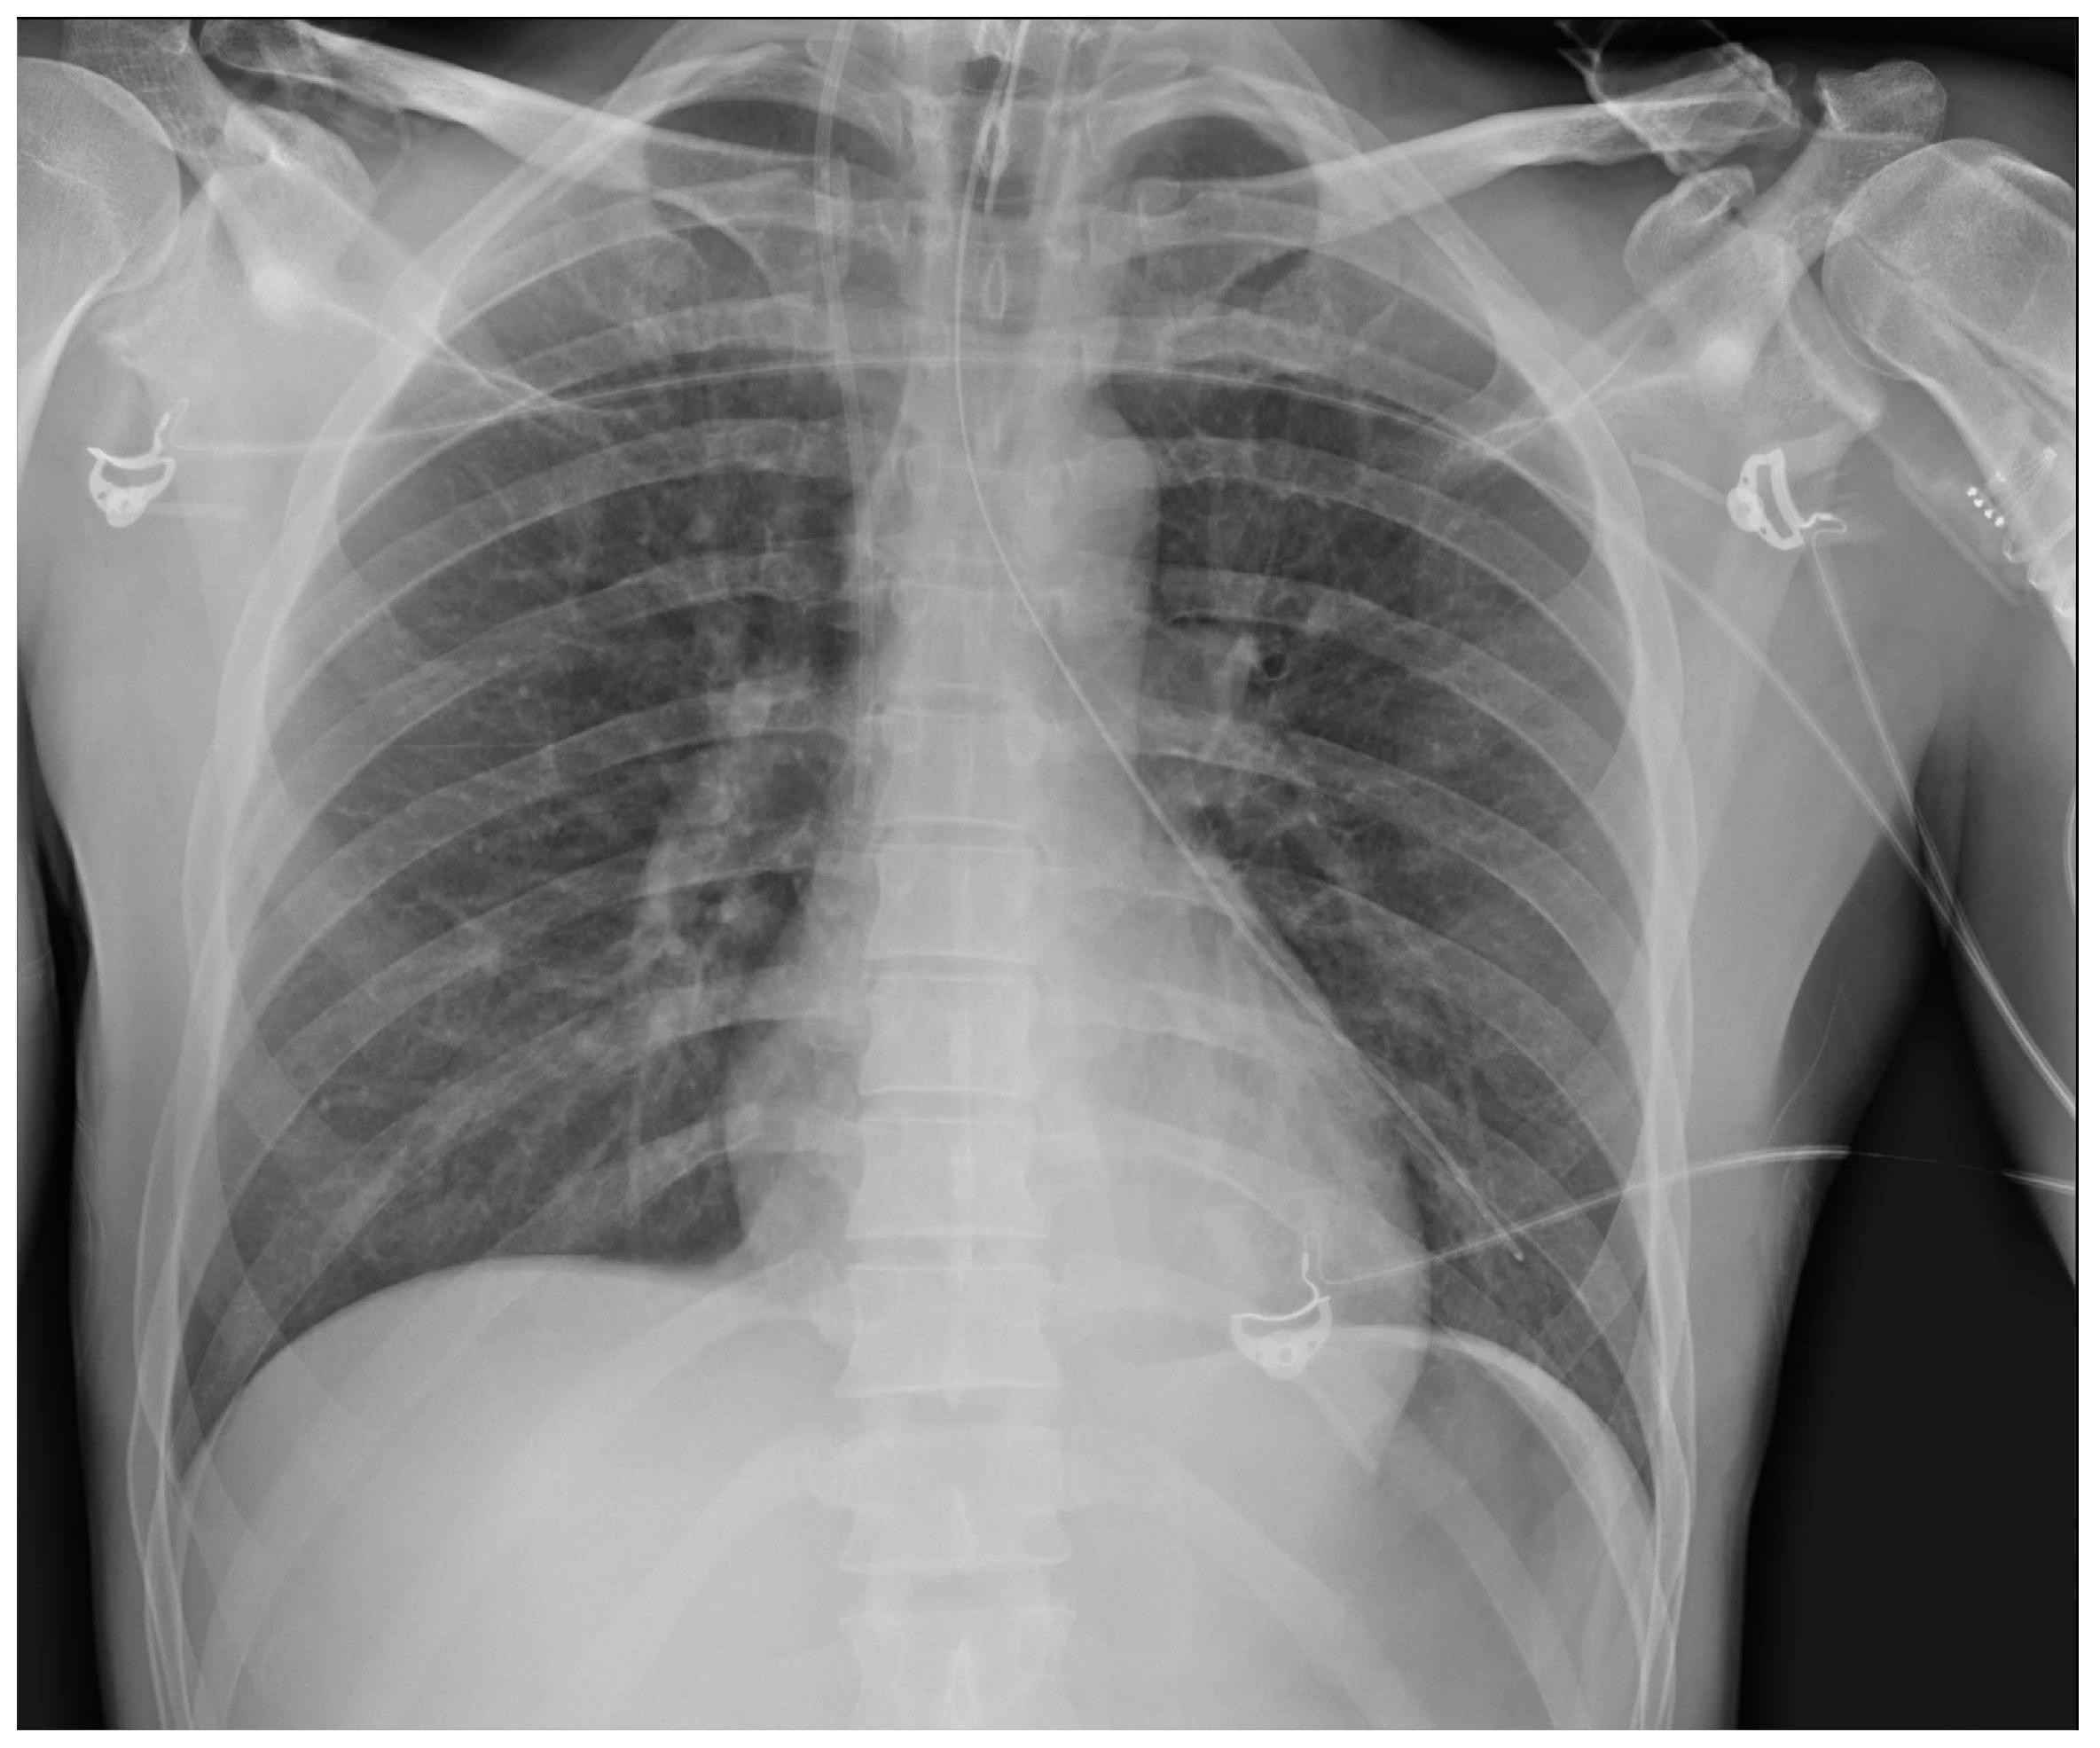

Insertion into the respiratory tree (Figure 27) (tip in the trachea/mainstem bronchus/lobar bronchus) can lead to subsequent aspiration pneumonia [37].

Figure 27.

Image of a mispositioned NG tube, whose tip entered the left mainstem bronchus down to the left lower airways; prompt recognition of such misplacement avoided any sequelae for the patient. This CXR also shows a right jugular CVC and an ETT.